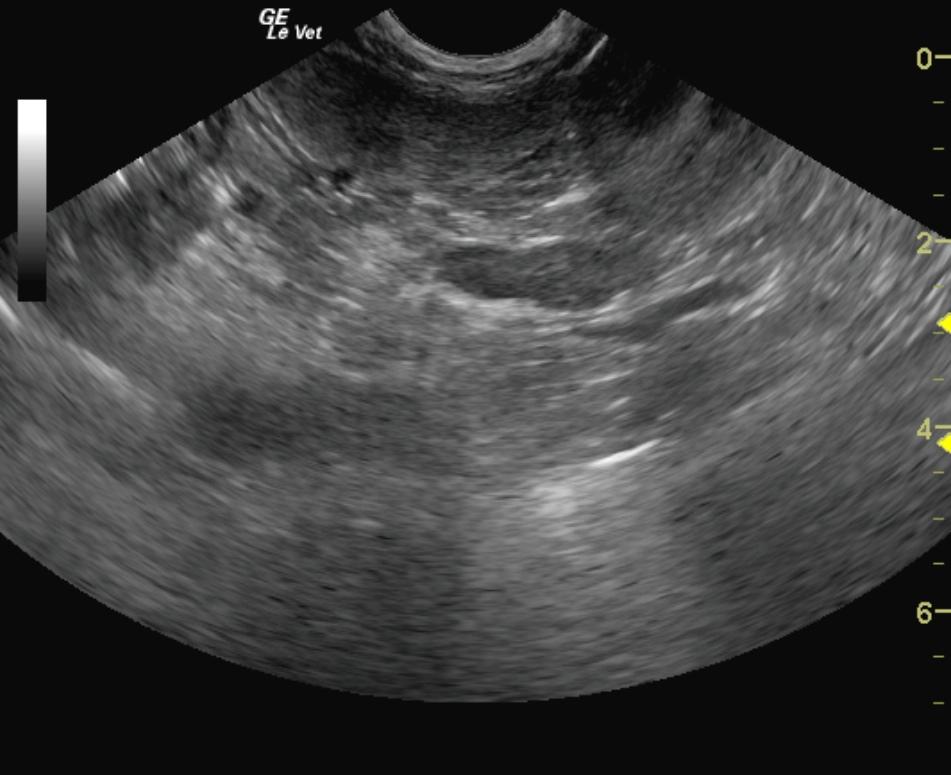

An 11-year-old FS dog was evaluated and presented for alopecia, panting, excessive water drinking, and polyphagia. Urinalysis and CBC were both within normal limits. Abnormalities on blood chemistry were hyperproteinemia, hyperphosphatemia, elevated GGT activity, elevated BUN:creatinine ratio, and hypercalcemia. An ACTH stimulation test was suggestive of hyperadrenocorticism.